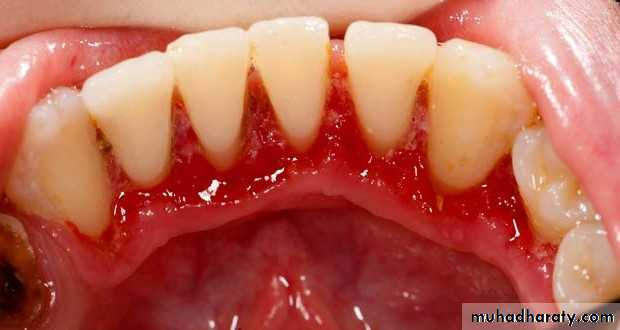

* Platelet defects :

a. Defect in the number of platelets( thrombocytopenia ).

b. Defect in the function of platelets

( thrombosthenia)

* Causes of thrombocytopenia :